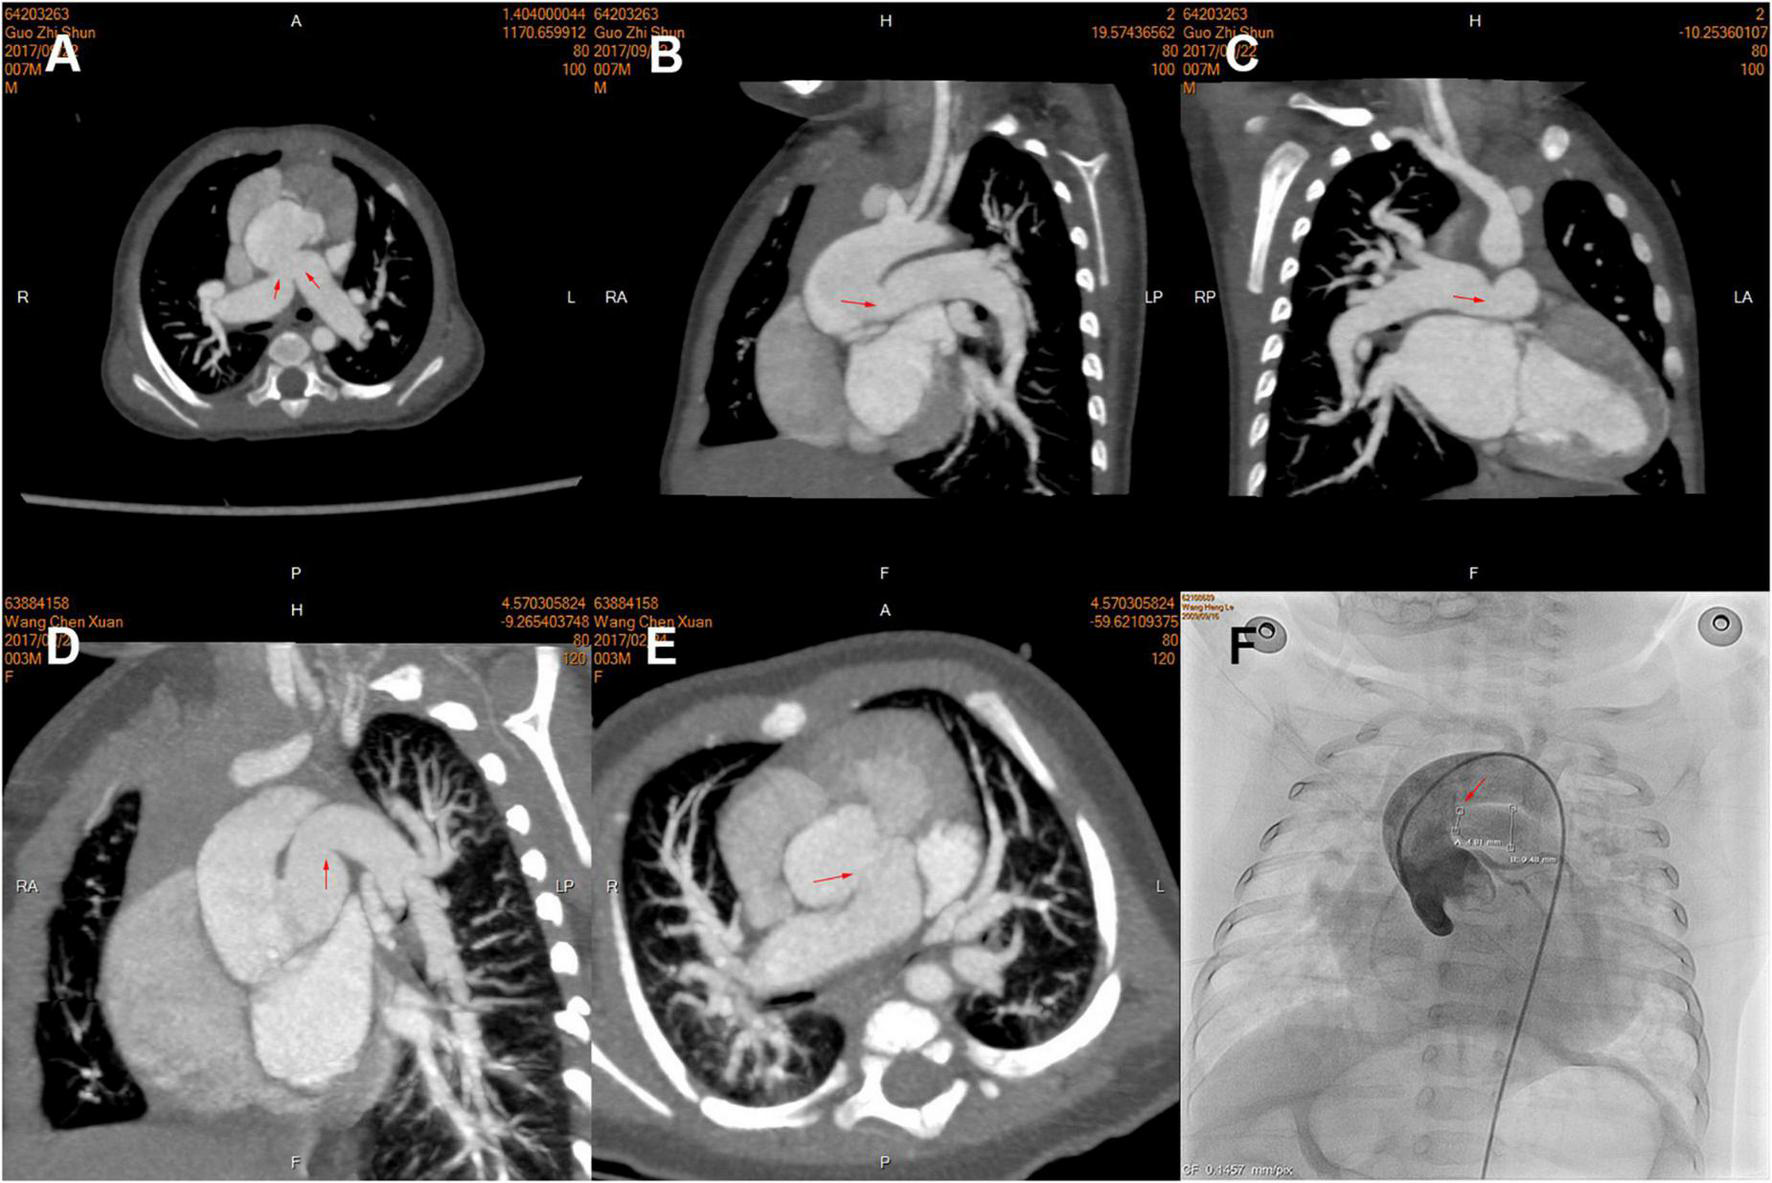

Pulmonary hypertension crisis affected twenty-two (22.4%) patients, all of which occurred in hospital; six patients died of post-operative PHC in the hospital, and one of them received ECMO after operation. We found patients with PHC often had larger bilateral PA size (indexed to Z-score) using logistic regression (Table 5) or both by imaging results in different truncal types (Figure 3). Thus, we identified the sum of Z-score of bilateral PAs > 4 (area under curve: 0.75, 95% CI: 0.61–0.91) as the optimal cutoff point for prediction of PHC by ROC. As expected, PHC occurred in 16 (51.6%) of the 31 children with a sum of Z scores of PAs greater than 4, while PHC occurred in only 6 (8.9%) of the remaining 67 children with Z scores less than 4. In addition, in patients with a sum of Z scores > 4, the mPAP was larger (54.9 ± 10.1 mmHg vs. 41.9 ± 15.6 mmHg, P = 0.04).

FIGURE 3

Pre-operative computed tomography (CT) angiography and cardiac catheterization showing branch pulmonary artery (PA) morphology of the different types of truncus arteriosus (TA), including the proximal and distal in three patients. (A–C) Type A2; (D,E) Type A1; (F) Type A3. The opening of branch PAs is labeled by red arrows.

First, dilated PAs were often an indicator of pre-operatively high PA pressure, which resulted from a combination of genetic predisposition, intrinsic characteristics of the vessel, and an adaptive response to elevated PA pressure. In patients with TA, bilateral pulmonary high-flow perfusion, induced by large PA size, was mainly due to the connection between PA and systemic circulation. The pre-operative mPAP in patients with larger PA size (sum of Z-score of PAs > 4) was also much higher. Prifti and colleagues also attributed it to increased blood flow into the lungs (20). Moreover, early PA hypertension is often reversible after surgery in patients younger than 6 months, which would become stubborn over time and lead to more exaggerated PA expansion. In patients older than 6 months, pre-operative median mPAP was higher (50 mmHg) and sum of Z-scores was larger (Z = 3.73). Of note, we found there was often a reactive constriction of the PA at the ostia of ascending aorta by CT. In addition, it was more common in dilated PAs, as shown in Figures 3A–C. We used the ostia/middle ratio of branch PA to describe the degree of constriction. The ratios of RPA and LPA were 0.95 and 0.93 in Group (sum of Z-score > 4) and 1.2 and 1.2 in the group (sum of Z-score < 4). In addition, median age of the former group was also older. In pathophysiology, pulmonary arteriole intimal fibrosis hyperplasia and PA dilatation often indicate the presence of late irreversible pulmonary hypertension. All of these could explain why these patients were at higher risk hazard of occurrence of post-operative PHC. More specific characteristics in morphology and hemodynamics should be of concern and investigated stepwise. We do not advocate the use of sum of Z-scores of PAs to screen for PA hypertension in children with TA. We recommend that it can be used to alert surgeons to this possibility so that further examinations and approaches may be performed if necessary.